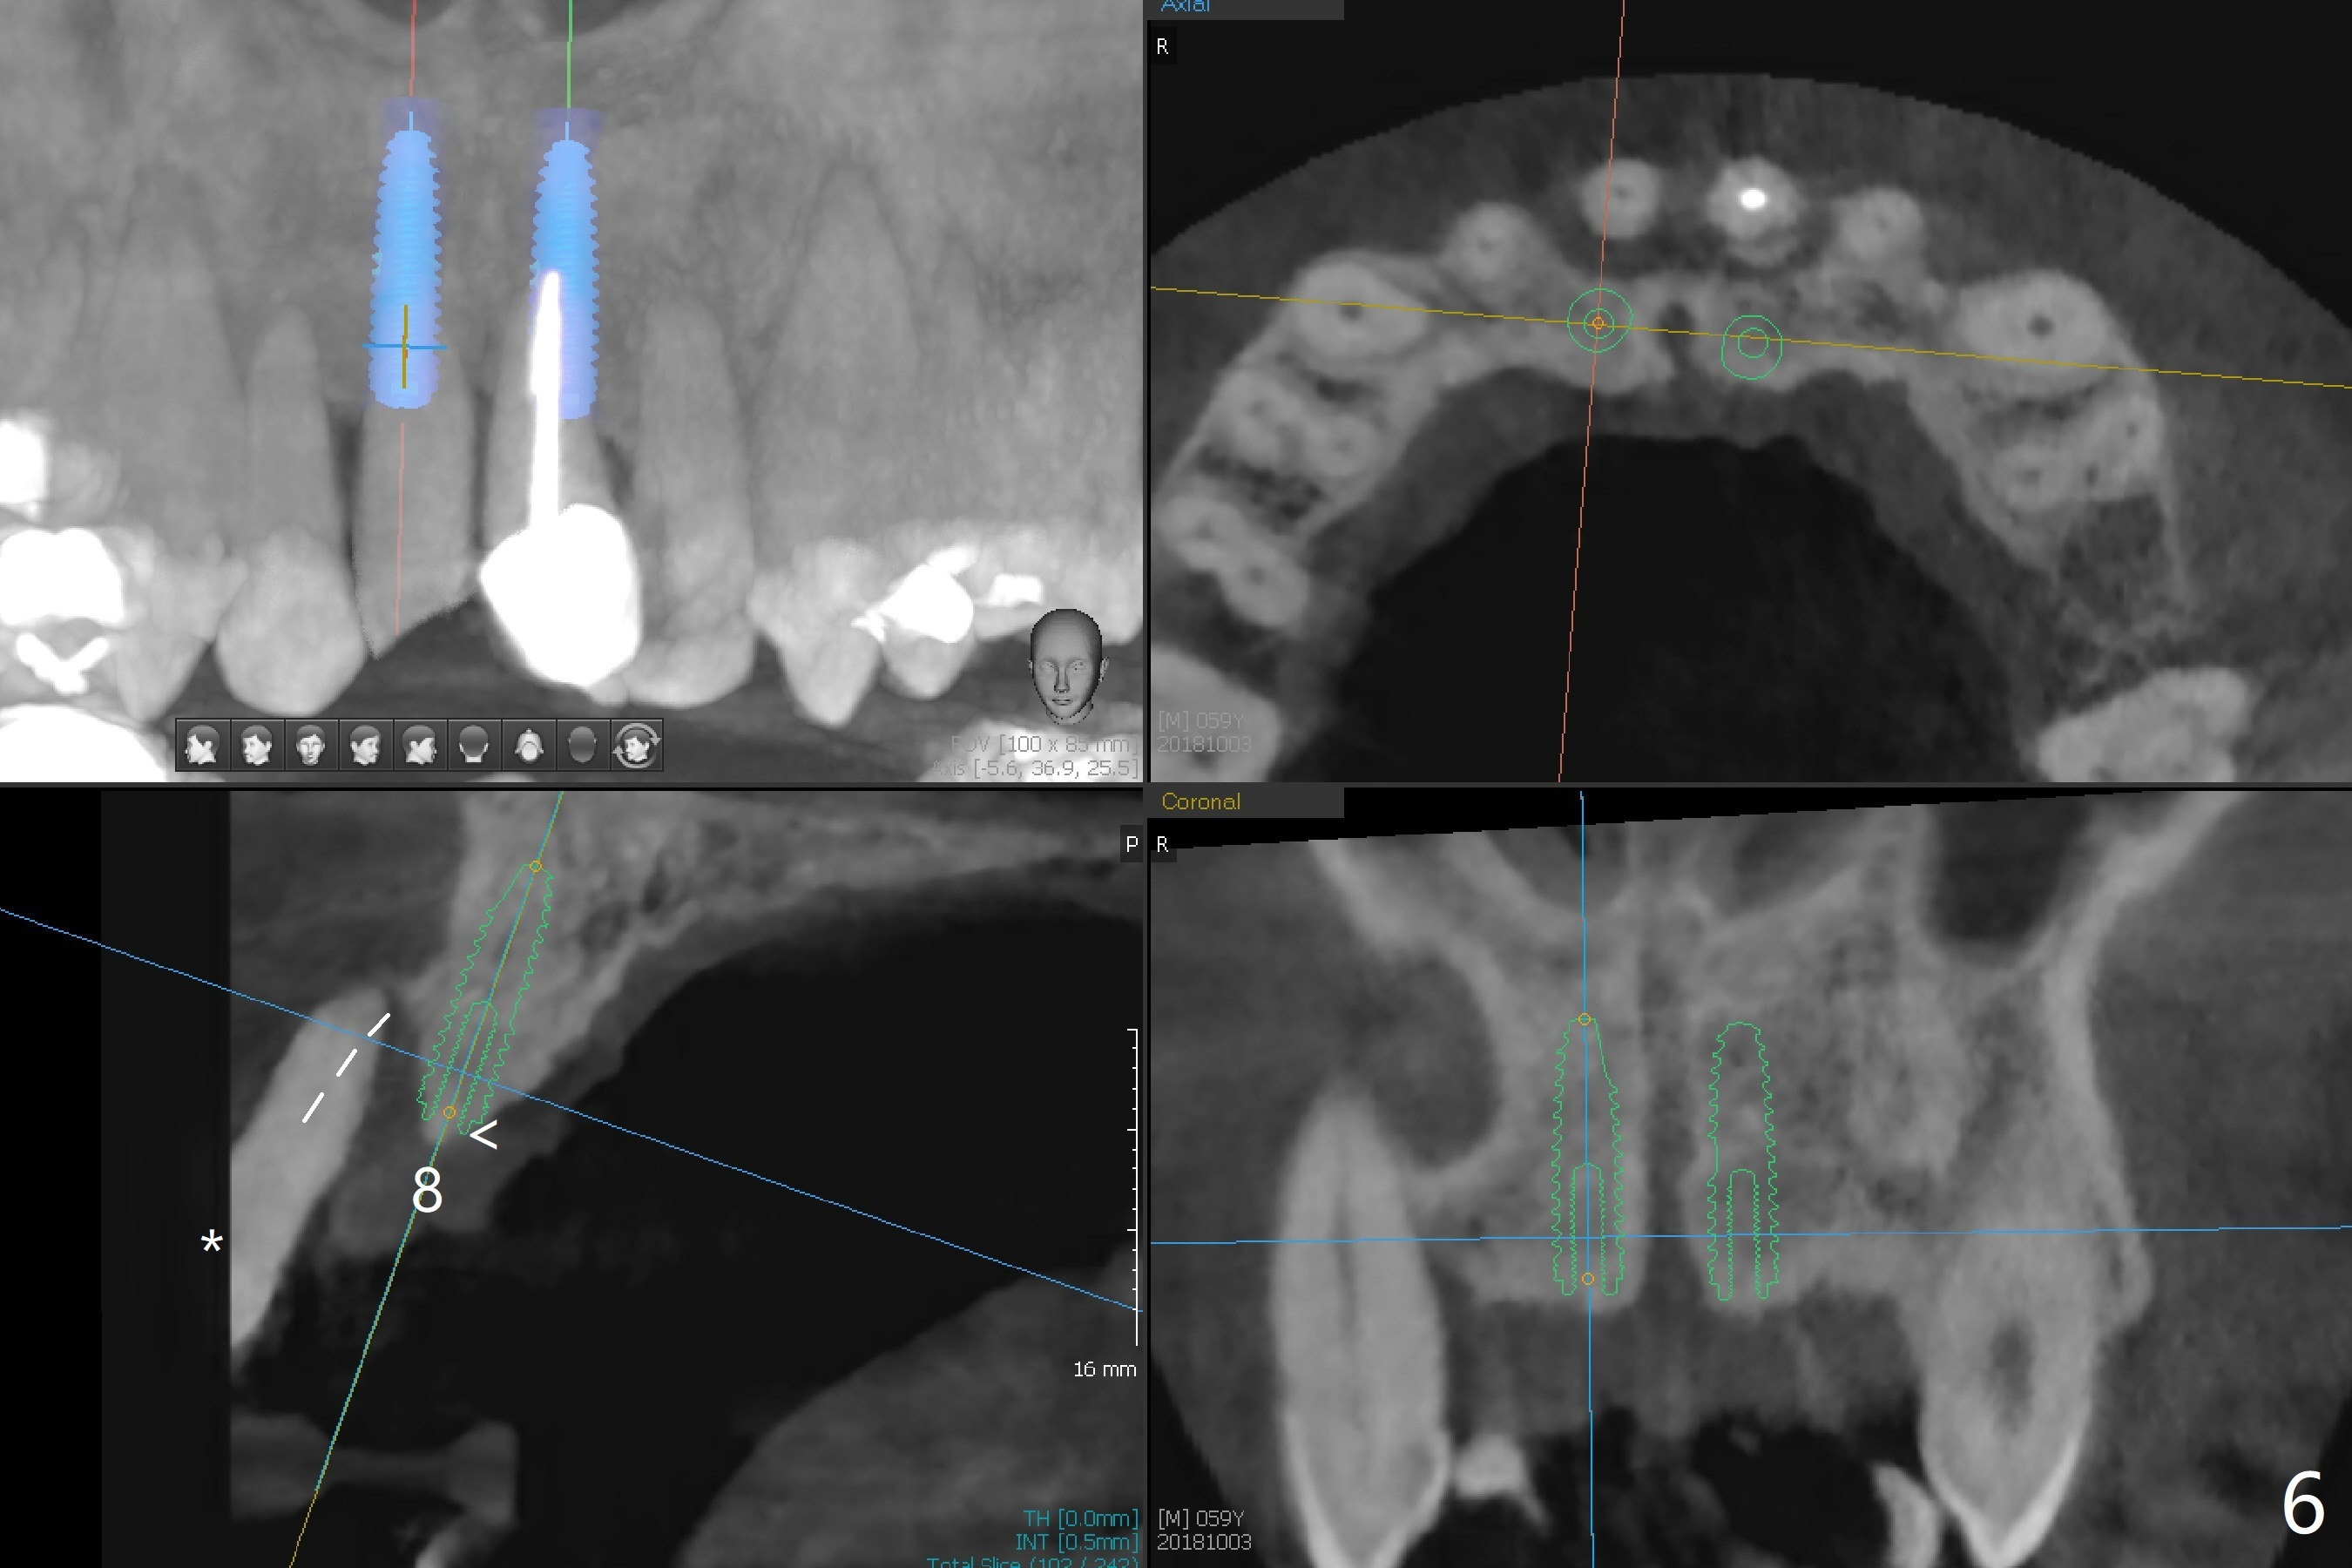

A 59-year-old man requests treatment for buccally displaced upper central incisors (Fig.1,2). It appears that the buccal plate is lost, but the bone height will allow placement of 3.5x13 mm implants with guide (Fig.3). Because of severe infection apical to the tooth #8 (Fig.4,5 *) and truncation of the incisal edges of the upper central incisors during CBCT taking (Fig.6,7 *), guided surgery may not be appropriate. The mesial surfaces of the teeth #7 and 10 and the incisal edges of the lower incisors (*) will be trimmed for immediate provisional. Immediate implants will be placed in the palatal crest of #8 (Fig.6 <) and close to the palatal crest of #9 (Fig.7). Angled abutments are expected (4.5x15 degree, A or B (4 mm cuff). PRF is to be preparedx2 (one for membrane; the other for sticky bone). Take Alginate impression when the patient returns for surgical stent.